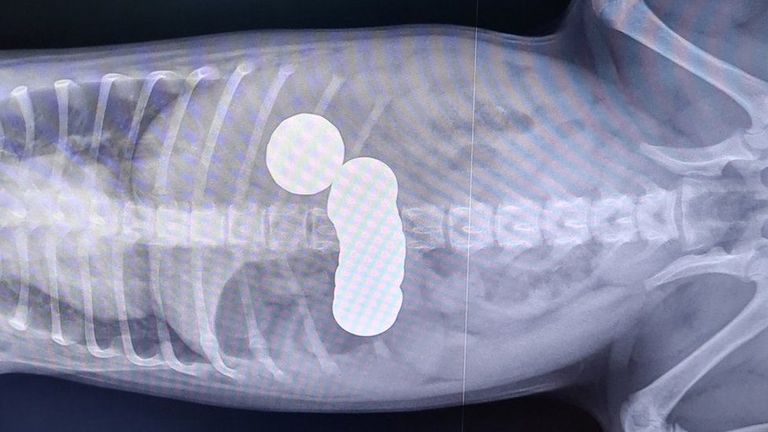

تم اصطحاب ديزي إلى الأطباء البيطريين حيث أظهرت صور الأشعة السينية أنه ابتلع العملات المعدنية.

وفحص الأطباء البيطريون ديزي ورأوا أن معدته تسبب له الألم، وأضافت جمعية الأطباء البيطريين الخيرية أنه شوهد بنسين من العملة البريطانية في قيئه، ما أثار الشكوك حول وجود انسداد، لذلك تم تخديره وتصويره بالأشعة السينية.

وأظهرت صور الأشعة السينية أنه ابتلع 20 قطعة نقدية من فئات مختلفة،